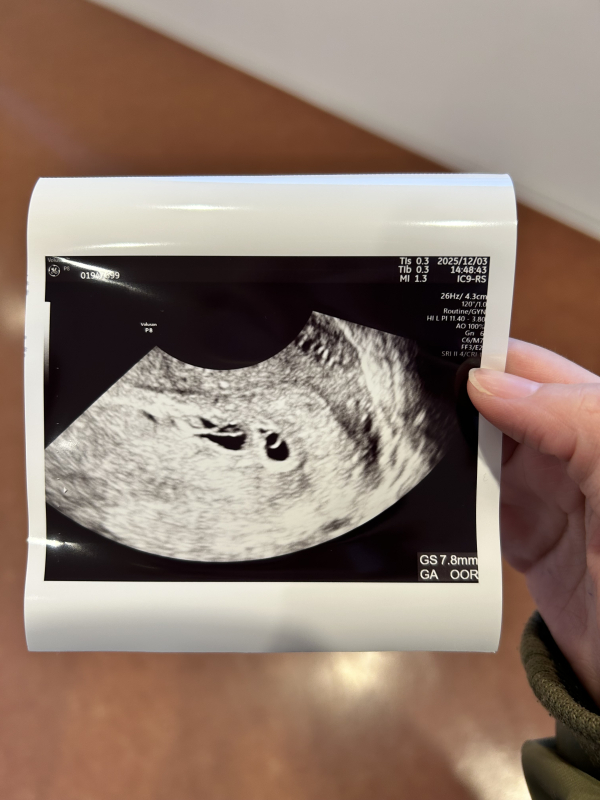

本日計算上では5w5dで初診でした。エコー写真がこちらだったのですがこれはなんでしょうか?こちらも緊張して言葉少なだったためか、お医者さんの方も特に何も言うことなく一枚こちらを渡され、また2週間後に来てくださいとしか言われませんでした。帰ってからこの二つ写っているものはなんなのだろう?と気になったのですが次回までの診察の2週間が長過ぎて…もしわかりましたら可能性だけでも教えていただけるとありがたいです。

お写真を拝見して、右側の黒い丸の方は、胎嚢で中に卵黄嚢と思われるものが写っているように思いました。

左側の長細い黒丸も胎嚢になるのか、どうなのかはっきりとしたことがわかりませんでした。